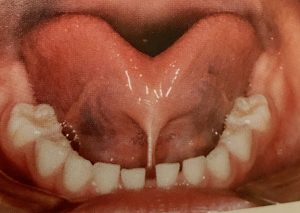

舌小帯の付着異常による咀嚼嚥下障害

摂食機能の習熟期に、舌小帯が短いことで舌を左右にうまく動かせないと食べ物の塊を臼歯に送ることができないため、咀嚼運動が適切にできなくなります。このような場合では、舌を口蓋に挙上できない代わりに嚥下時に舌を前方に突出してしまいます。

発音障害

舌小帯付着異常があると、構音が完成する5歳から6歳ごろまでに発音がうまく獲得されないことがあります。

具体的には舌尖を用いて発音する さ、た、な、ら行などが舌足らずな発音になります。

まずは舌正体を伸展させるトレーニングや切除1週間後に舌の挙上訓練と舌筋の強化を行い、舌の運動範囲を広げていきます。これにより舌小帯付着異常による発音障害の改善が期待できます。